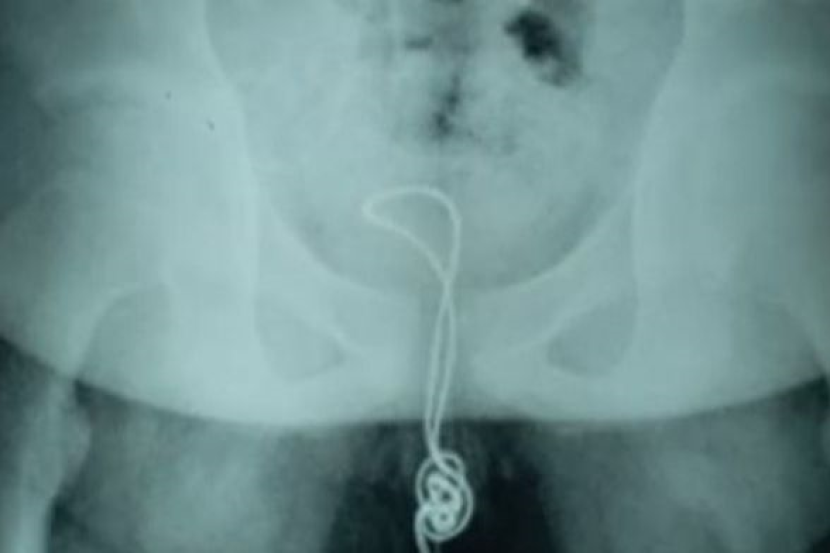

SEORANG remaja berusia 13 tahun bertindak memasukkan kabel USB dalam zakarnya dan doktor terpaksa melakukan pembedahan selepas ia tersangkut pada pundi kencing.

Remaja itu, yang namanya tidak didedahkan, memasukkan kabel berukuran kira-kira 20cm itu ke dalam zakarnya sebelum menyedari dia tidak dapat menariknya semula.

"Kabel itu terkena pundi kencingnya, berselirat dan akhirnya bersimpul, jadi apabila dia cuba menariknya semula, ia tersekat."

Mereka memotong pundi kencingnya untuk mengenal pasti kabel yang bersimpul, memotong bahagian berselirat dan mengeluarkan kabel selebihnya melalui zakarnya, cara yang sama ia dimasukkan.